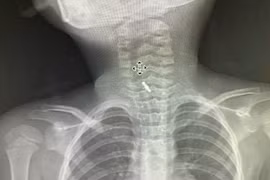

Suýt thủng phế quản vì mảnh xương cá đi lạc

Dị vật đường thở là tai nạn không hiếm gặp ở trẻ nhỏ và người lớn tuổi. Người trưởng thành cũng có thể gặp phải nếu ăn vội, nói chuyện hoặc cười trong lúc ăn.